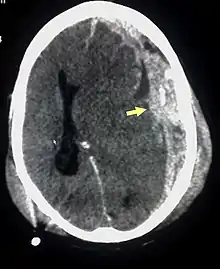

SBS poate fi greșit diagnosticat sau nediagnosticat, ori cei responsabili cu creșterea copilului pot minți, conștienți fiind de cauza leziunilor. De obicei, nu există semne exterioare vizibile.[2] și nu există stabilit nici un set de simptome care să indice aceasta.[7] Examinarea de către un oftalmolog cu experiență este adesea critică în diagnosticarea SBS, formele particulare de hemoragii oculare fiind destul de caracteristice.[15] Nici o stare patologică alternativă nu imită exact toate simptomele de SBS, dar SBS nu poate fi exclus la copii care se prezintă cu hidrocefalie, sindromul morții subite a sugarului (SMSS) sau „moartea în pat”, tulburări de izolare sau boli infecțioase ca meningită și tulburări metabolice.[14][16] Computerul tomograf (CT) și imagistica prin rezonanța magnetică nucleară (RMN) sunt folosite pentru a diagnostica leziunile cerebrale.[2] Afecțiunile care pot însoți SBS includ: fracturi traumatice la nivelul coloanei vertebrale cervicale, hemoragie retiniană, hemoragie cerebrală sau atrofie cerebrală, hidrocefalie și edem papilar.[7]

Tratamentul implică monitorizarea presiunii intracraniene și evacuarea lichidului cefalorahidian, dacă presiunea este ridicată iar dacă un hematom intracranian este prezent, drenarea acestuia[7].